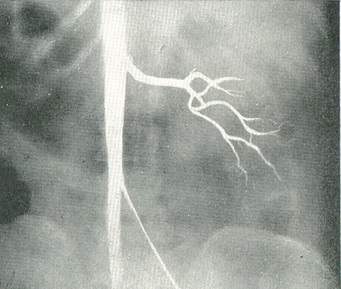

Якщо поряд з аплазією нирки є повна аплазія сечоводу, то при цистоскопії відсутнє відповідне устя сечоводу і навіть половина протоки трикутника. У скрутних випадках сумнів дозволяє пневморен, пневморетроперитонеум або ангіографія нирки, якими констатовано відсутність тіні однієї з нирок і її судин (рис. 49).

Рис. 49. Аплазія лівої нирки. Ангіограма - відсутність магістральних ниркових судин ліворуч.